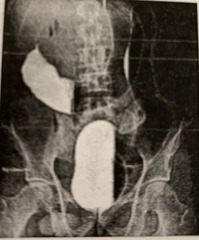

absence of parasympathetic ganglia, usually in the distal colon, resulting in the absence of peristalsis

Hirschsprung disease

Achalasia

Back

failure of smooth muscle of alimentary canal to relax